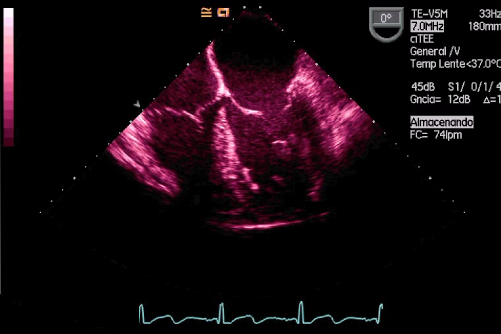

Curso de ecografía crítica en todas sus modalidades (ecocardiografía transtorácica y transesofágica, ecografía pulmonar, vascular, cerebral, FAST) dirigido a: médicos intensivistas, emergenciólogos, anestesiólogos, internistas, médicos de familia, neumólogos, cardiólogos y a todo aquel interesado por utilizar la ecografía como parte del examen físico del paciente crítico.

En nuestro afán por seguir el trabajo empezado hace ya varios años desde Europa (España) por impulsar la ecografía crítica para intensivistas, emergenciólogos, anestesistas, internistas, subespecialistas de obstetricia crítica, neumólogos y todo aquel médico interesado en aprender a utilizar la ecografía como parte de su examen físico, ahora desde Centroamérica (Panamá), hemos escrito el primer libro Latinoamericano-Europeo de ecografía crítica sub-especializado y dedicado exclusivamente al paciente con shock de cualquier etiología (obstructivo, distributivo, cardiogénico, hipovolémico) que involucra todas las modalidades ecográficas: ecocardiografía, ecografía pulmonar, vascular, abdominal, del sistema nervioso central/doppler transcraneal, etc) en el que participan muchos expertos en sus respectivas áreas tanto de Europa como de América y también algunos profesores del EDEC (Diploma Europeo de ecocardiografía / ESCIM- Sociedad Europea de Medicina intensiva).